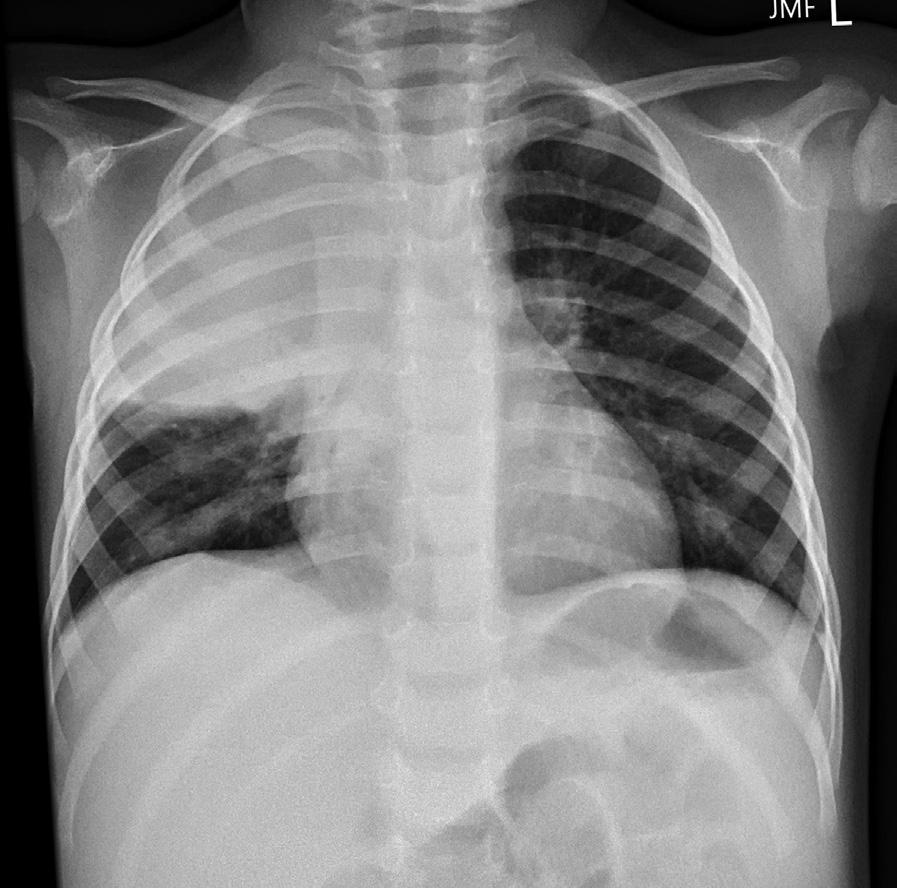

Understanding lung topography is useful in both diagnosing and localizing disease. For example, a 2-year-old boy presents with a 2-day history of fever, cough, and recent onset of tachypnea (an increased respiratory rate). On examination, there are intercostal muscle retractions and nasal flaring, and the child appears ill. On auscultation, breath sounds are decreased over the right upper lobe anteriorly.

A chest x-ray reveals opacification (known as consolidation) over the right upper lobe anteriorly consistent with lobar (specifically right upper lobe) pneumonia.